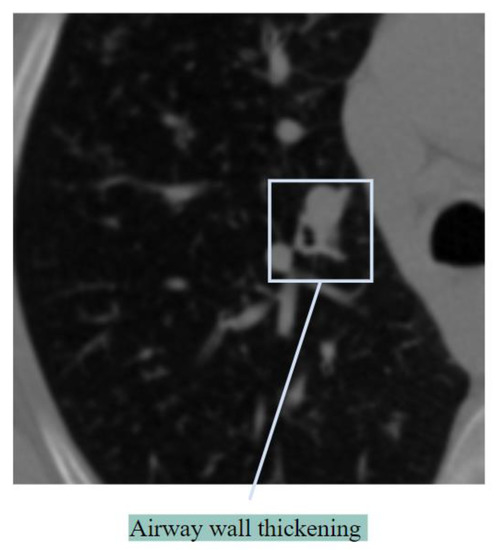

Airway Wall Thickening

Bronchial wall thickening, which can result in airflow blockage, is another indicator of lung abnormalities [25]. Airway wall thickening generally occurs in inflammation of the airways. Figure 5 shows airway wall thickening.

Figure 5. Airway wall thickening.

Two pathological mechanisms, bronchial obstruction and airway wall inflammatory destruction, result in damage to bronchial wall structures [26]. Bronchial wall thickening is also associated with severe cases of COVID-19.